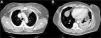

Mujer de 60 años, no fumadora, sin antecedentes de inmunosupresión ni factores de riesgo neumológicos. Acudió a urgencias por dolor pleurítico y en hombro izquierdo, fiebre de 38°C, tos sin expectoración e intenso dolor en la región medioclavicular y el hombro izquierdo. La radiografía de tórax mostró tenue infiltrado en el lóbulo inferior izquierdo (LII). A la exploración destacaba semiología de condensación y egofonía en campo inferior izquierdo. Presentaba una zona abultada muy dolorosa no fluctuante, sin signos inflamatorios en piel, en la región esternoclavicular izquierda alta. Se realizó fibrobroncoscopia, que mostró signos inflamatorios, y se remitieron muestras para anatomía patológica y microbiología. Los hemocultivos fueron negativos. El ecocardiograma no mostró lesiones valvulares ni vegetaciones sugestivas de endocarditis. Se inició tratamiento empírico con ceftriaxona y levofloxacino, con escasa respuesta clínica, precisando la administración de mórficos para control del dolor. La tomografía axial computarizada (TAC) torácica mostró cambios inflamatorios en el músculo pectoral izquierdo e imagen pseudonodular de 3,3×2,3cm, que se introducía entre la porción anterior del primer y segundo arco costal izquierdo, además de condensación pulmonar en LII con derrame pleural acompañante (fig. 1). Tanto la ecografía de cuello como la gammagrafía ósea confirmaron los hallazgos. Se realizó punción-aspiración con aguja fina (PAAF) guiada por ecografía, de la que se aisló S.aureus resistente a ampicilina y sensible a eritromicina, gentamicina, clindamicina, ciprofloxacino, levofloxacino y cotrimoxazol. En las muestras de la fibrobroncoscopia se aisló el mismo microorganismo. Durante el ingreso recibió tratamiento antibiótico intravenoso, según antibiograma, con ciprofloxacino y amoxicilina-clavulánico con mejoría clínica, radiológica y de los reactantes de fase aguda, sin precisar drenaje. Fue tratada de forma ambulatoria durante 40días con resolución completa del cuadro.